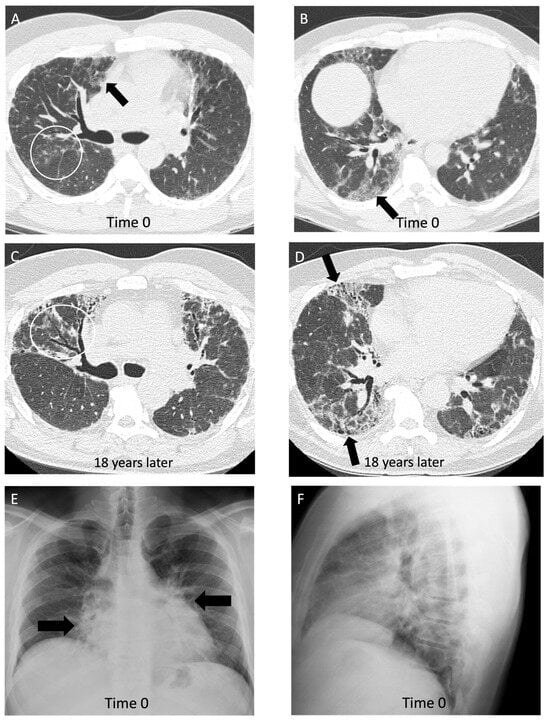

Figure 5.

A 43-year-old non-smoking male with 15-year history of tungsten carbide exposure as a metal grinding tool maker, diagnosed with hard metal lung disease, which was confirmed with surgical lung biopsy. (A,B) Axial computed tomography images demonstrate patchy ground glass opacities (arrows) and small centrilobular nodules (white circle) with minimal architectural distortion and traction bronchiectasis; (C,D) computed tomography images 18 years later demonstrate long-term evolution of fibrosis, with development of traction bronchiectasis (white circle) and mild honeycombing (black arrows) on the background of ground glass opacity and coarse reticulation; (E) posteroanterior view and (F) lateral view chest radiographs show a perihilar and lower lung zone predominant reticular abnormality (black arrows); (G) posteroanterior view and (H) lateral view chest radiographs 18 years later demonstrate a reduction in lung volumes, and the prior interstitial opacities appear coarser and more prominent, particularly in the perihilar lung (white arrows).